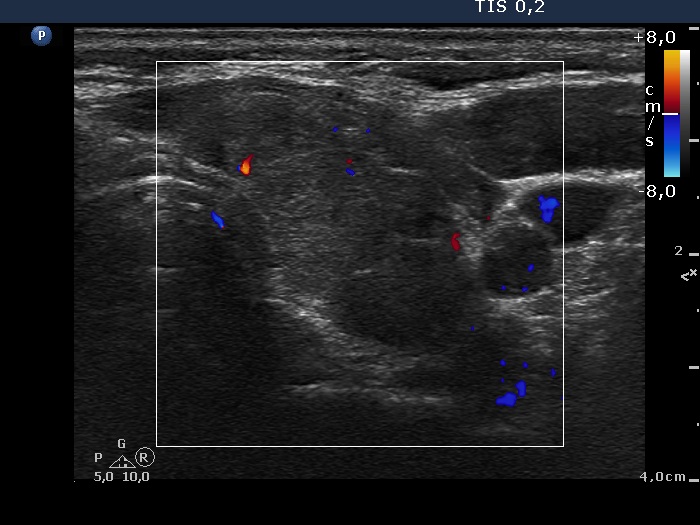

Left lobe, transverse scan, color Doppler mode. The vascularization is not specific.